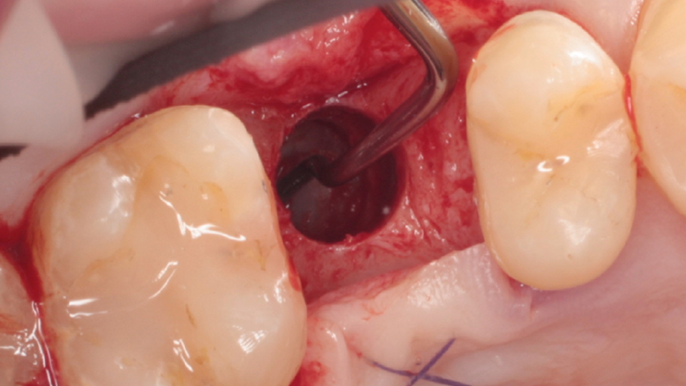

Clinical case: # 46 implant placement & GBR using i-Gen membrane for significant vertical resorption & mixed bone defect

- Courtesy of Dr. Iulian Filipov, Romania -

AnyRidge, mandibular posterior, i-Gen, resorption, bone defect, bone regeneration, space management, #46, GBR, Dr. Iulian Filipov

AnyRidge implant system, i-Gen

“AnyRidge KnifeThread achieves excellent stability in regenerated bone & even in only 3mm bone height!”